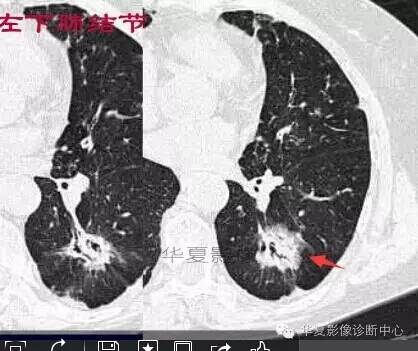

这一例是否GGO成分几乎没有

基本是实性的

那就按实性的分析

胸膜凹陷,分叶征